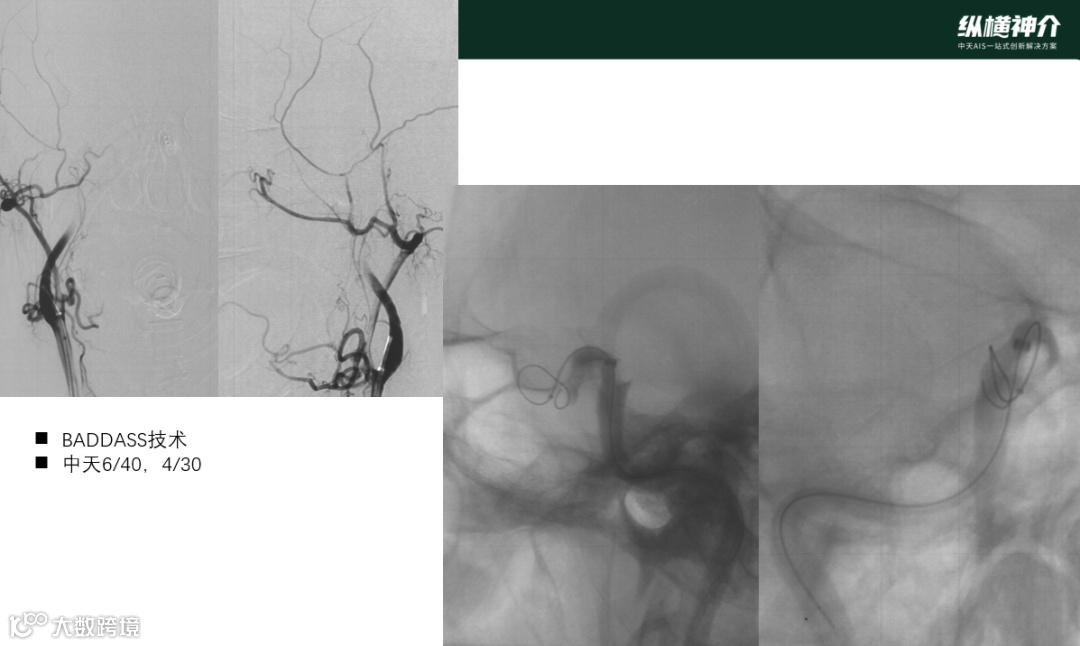

BADDASS technique

球囊导引导管到颈内动脉C1以远,起到支撑和通路作用;微导管通过J型微导丝穿过血栓进入右侧大脑中动脉的下干远端;选择相对长的天弋®取栓支架,远端2/3超越血栓段,避免近端支架太长,影响后续中间导管推进。使用长支架的目的是保证不那么精确释放下支架仍留有余地;通过常规微导管和主动推挤技术来释放支架,提高贴壁性和与血栓嵌合性;移除微导管,最大限度提高抽吸内腔;通过支架锚定和推送导丝将抽吸导管推送至血栓近端;通过释放和轻推支架推送导丝来释放推送导丝的牵拉力;充盈BGC并保证远近端同时负压抽吸;取栓支架和抽吸导管作为一个单位整体撤出。34

图7:BADDASS技术